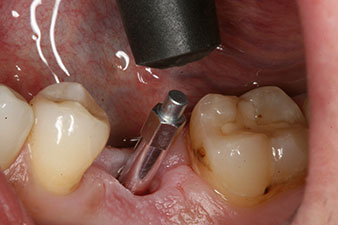

The torque used for the machine-driven placement was 43 Ncm. In addition, after screwing a measuring post (SmartPeg) specially matched to the implant, the ISQ value was measured with the probe of the W&H Osstell ISQ module.

This module is an optional extra for the W&H Implantmed and is docked to the implantology motor (see Fig. 11). The dimensionless ISQ value immediately after insertion was 64 orovestibular and 68 mesiodistal (maximum value = 100).

The implant was uncovered two months later and a gingiva former was screwed in (no picture).